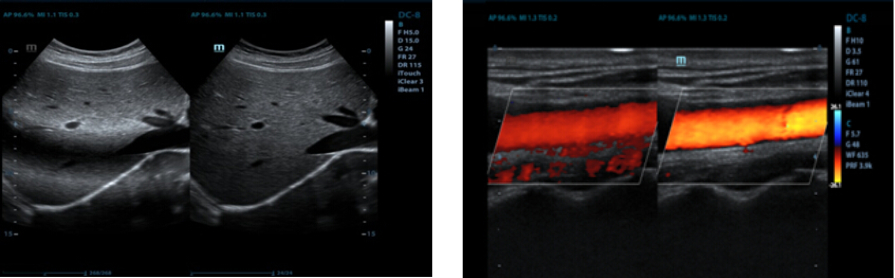

Auto IMT (Intima-Media Thickness)

Auto measurement of anterior and posterior wall thickness to accurately evaluate carotid status.